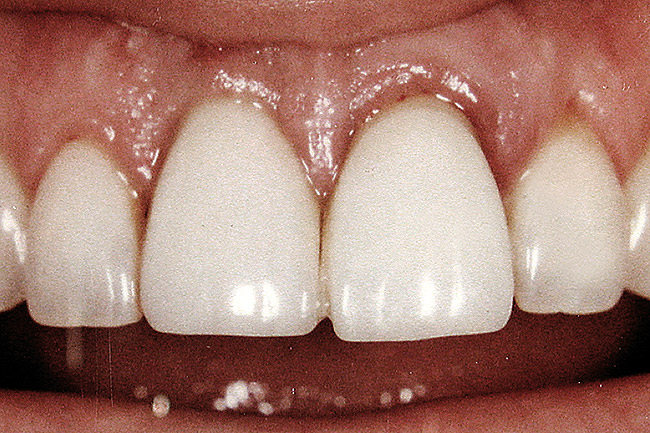

Figure 7  Because the interproximal crestal bone was maintained and the soft tissue supported at the time of tooth removal, an excellent interimplant papilla exists.

Figure 7

Figure 9  The final restorations exhibit a minimal 1-mm to 1.5-mm change in papilla height when compared with the pre-extraction height.

Figure 9